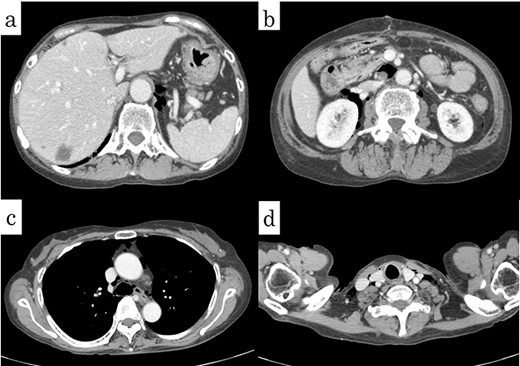

On chest and abdominal CT, free gas was observed in the entire abdominal cavity (Fig. 1a), and extensive emphysema was also observed in the retroperitoneum (Fig. 1b). In addition, it was observed from the mediastinum to both sides of the necks (Fig. 2).

Preoperative CT showed (a) pneumoperitoneum (arrows) and (b) a massive pneumoretroperitoneum (arrows).